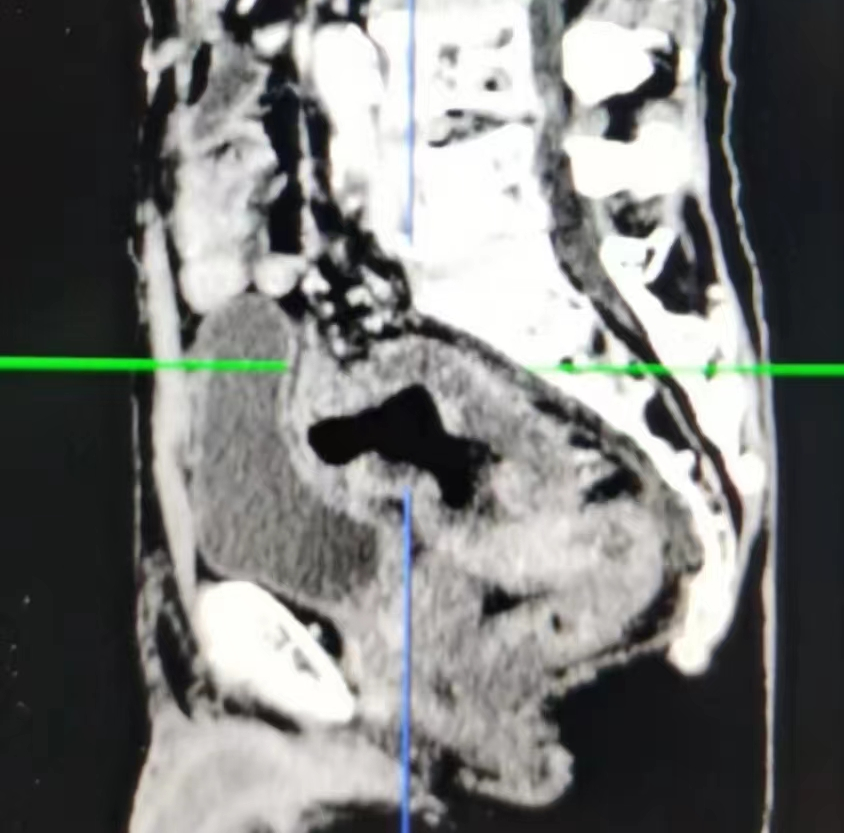

一位80岁高龄患者在一年余前于家中无明显诱因下突发腹部胀痛不适,疼痛呈阵发性,不剧,当时未予以重视。之后反复腹胀腹痛一年多,后期每日解大便数次较前增多,且每次解大便不通畅、不尽感明显。由于老年人对该疾病不敏感,一直误以为肠胃炎,没有及时就医。近期上述症状较前明显加重,遂来温州市中心医院就诊住院,查肠镜发现直肠内一较大的不规则隆起肿块,易出血,已造成肠腔狭窄梗阻,肠镜活检病理提示直肠腺癌。且进一步的腹部CT、MRI检查发现直肠肿瘤已明显侵犯右侧输尿管,导致右肾积水、右输尿管明显扩张。

CT检查